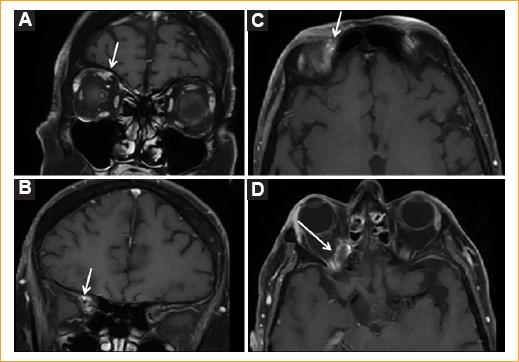

La segunda RM realizada un mes después de la primera reveló un engrosamiento del nervio frontal derecho desde la fisura superior orbitaria hasta el seno cavernoso (Fig. 3). Estos hallazgos, dentro del contexto clínico del paciente, llevaron al diagnóstico de infiltración carcinomatosa del nervio frontal derecho.

Figura 3 Técnicas de RM de alta resolución de cerebro y órbitas. A y B: las secciones coronales en secuencia T1 con FAT SAT con contraste con gadolinio muestran el engrosamiento del nervio frontal en su trayectoria intraorbitaria (A está en relación a los músculos y B a la trayectoria de la fisura orbitaria superior). C y D: secciones axiales en secuencia T1 con FAT SAT con contraste con gadolinio C: se aprecia el nervio engrosado en su trayectoria superior cerca del foramen supraorbitario y D: su trayectoria intraorbitaria.